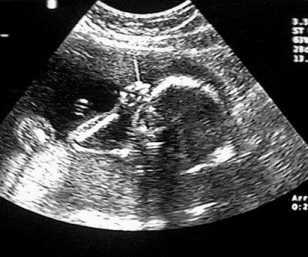

The same technique can be used to probe biological tissues: by determining the time delay from pulse emission to echo detection, one can determine the depth of reflecting tissue layers. Furthermore, by knowing the acoustical impedance (discussed in Topic 3) of each layer, we can even determine the percent of the ultrasound intensity that is reflected by each of those layers. The reflectivity aids us in characterizing which type of tissue is reflecting the ultrasound waves. A typical ultrasound scan is shown below in Figure 4.

(a)A typical 2D real-time image obtained during an ultrasound scan.

(b)A 3D reconstruction derived from multiple 2D scans

Figure 4:Examples of ultrasound imaging.